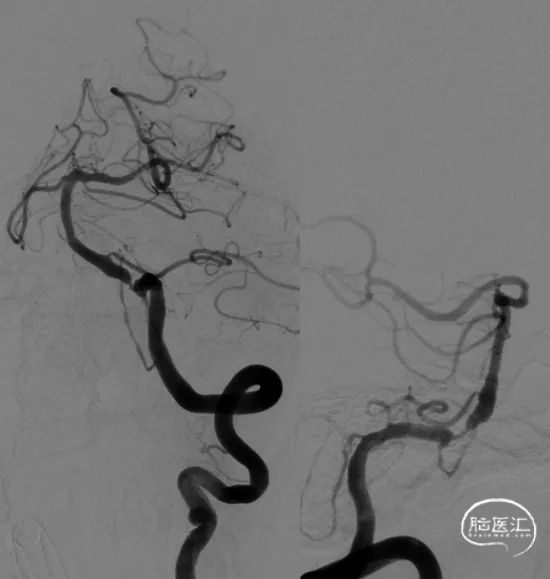

术前影像。

考虑到血管严重扭曲,以长鞘和6FNavien建立路径,微导丝、微导管通过病变。

微导管造影确认真腔。

球囊到位。